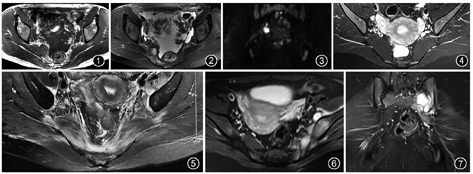

肿瘤导致的PS症状主要源于骨盆与坐骨大孔区域骨与软组织肿瘤压迫、侵犯坐骨神经。MRI显示,恶性肿瘤多边界不清、边缘不规则,向周围组织浸润生长;良性肿瘤多边界清楚,对周围组织形成压迫。梨状肌的恶性肿瘤多为转移瘤,如宫颈癌、结直肠癌转移(图1,图2,图3);原发恶性肿瘤可见淋巴瘤及间叶组织肿瘤;良性肿瘤可见脂肪瘤,韧带样瘤虽有一定侵袭性,但仍为良性肿瘤。源于骨盆的肿瘤可见交界性肿瘤如骨巨细胞瘤、恶性肿瘤如脊索瘤[16,17,18]。源于坐骨神经的良性肿瘤如神经鞘瘤表现为坐骨神经走行区边界清楚的囊或实性肿块,T1WI呈低、稍低信号,T2WI呈高、稍高信号;神经根鞘囊肿表现为坐骨神经边界清楚囊状T1WI低、T2WI高信号病变[19,20]。此外,部分恶性肿瘤患者在治疗过程中可能出现PS症状,如本院一宫颈癌患者在放疗过程中出现臀部疼痛,MRI表现为双侧梨状肌水肿(图4,图5)。放疗所致PS虽非主要病症,但MRI可为患者治疗不良反应提供客观依据,辅助临床医生评估并及时调整治疗方案。

感染是PS重要病因之一,以骶髂关节、髋关节化脓性炎或结核累及同侧梨状肌最为常见。化脓性炎症以金黄色葡萄球菌感染为主,其他如沙门氏菌感染亦有报道。患者除PS症状外,全身可有寒战、高热,实验室检查血白细胞及C反应蛋白升高、红细胞沉降率加快。MRI可见骨质与梨状肌边界不清,T2WI高信号影,关节间隙变窄,关节腔积液,重者可见脓肿压迫、刺激坐骨神经,表现为边缘光滑、信号混杂的囊性病变,增强扫描呈明显环形强化;除梨状肌与骨盆感染表现外,亦可因炎症刺激坐骨神经使神经鞘增粗,T2WI呈高信号[21,22]。骶髂关节与髋关节结核发病较化脓性炎症缓慢,患者可有全身中毒症状,MRI显示受累骨质破坏并累及梨状肌呈T1WI低、T2WI高信号,骨旁可形成冷脓肿压迫梨状肌与坐骨神经(图6,图7)。腰椎结核形成冷脓肿亦可向下流注累及梨状肌和坐骨神经[23]。感染所致PS患者在全身症状背景下有臀、腿部疼痛时,MRI可显示感染病灶,从而尽早作出诊断。此外,免疫系统疾病可致梨状肌炎性病变,以强直性脊柱炎最常见,除骶髂关节边缘毛糙、关节间隙狭窄、关节面下骨质水肿等骶髂关节炎表现外,可见邻近梨状肌肿胀、坐骨神经及臀上、臀下神经增粗、T2WI高信号等炎症表现[3]。